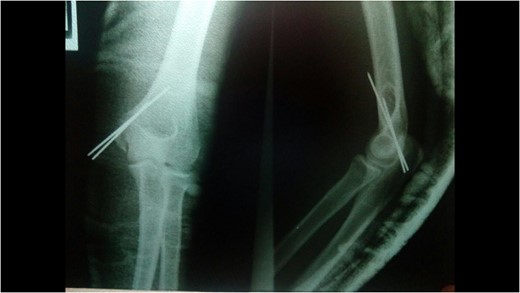

A 14-year-old male patient presented to the emergencies department complaining of intense pain in the left elbow secondary to a fall with an outstretched hand while practicing soccer. He had no significant comorbidities. At physical examination he presented with deformity located on the left elbow, he was unable to passively or actively mobilize it, he reported paresthesias and diminished sensation located on the fifth and fourth digit. X-rays showed a dislocation on the left elbow and an avulsive fracture of the medial epicondyle of the distal humerus (Fig. 1). He was taken to the operating room where a closed manipulation was performed; however the reduction was not achieved due to the interposition of the fractured medial epicondyle. A medial approach to the elbow was performed; intra-operative findings included rupture of the medial capsule and intra-articular interposition of the fragment of the medial epicondyle with a posterolateral dislocation of the elbow, the ulnar nerve showed compressive injuries at the site of the fracture (Fig. 2). Extraction and fixation of the interposed intra-articular fragment was performed followed by elbow reduction and a medial capsule repair, without ulnar nerve transposition (Fig. 3). The patient was left with a posterior splint for a month. After a 3 month follow-up, he has recovered full range of motion of the elbow with recovery of strength and sensation over the distribution of the ulnar nerve.

X-rays showing the result of the first attempt of closed manipulation and open reduction.

We decided to fix the fragment with k-wires taking in account of the frequent complications of the use of screws, such as the need of hardware removal in almost 20% of patients of the larger case series revised, however the use of screws has been recommended, especially in cases with older patients, mainly to gain stability and allow early range of motion [3, 7–9].